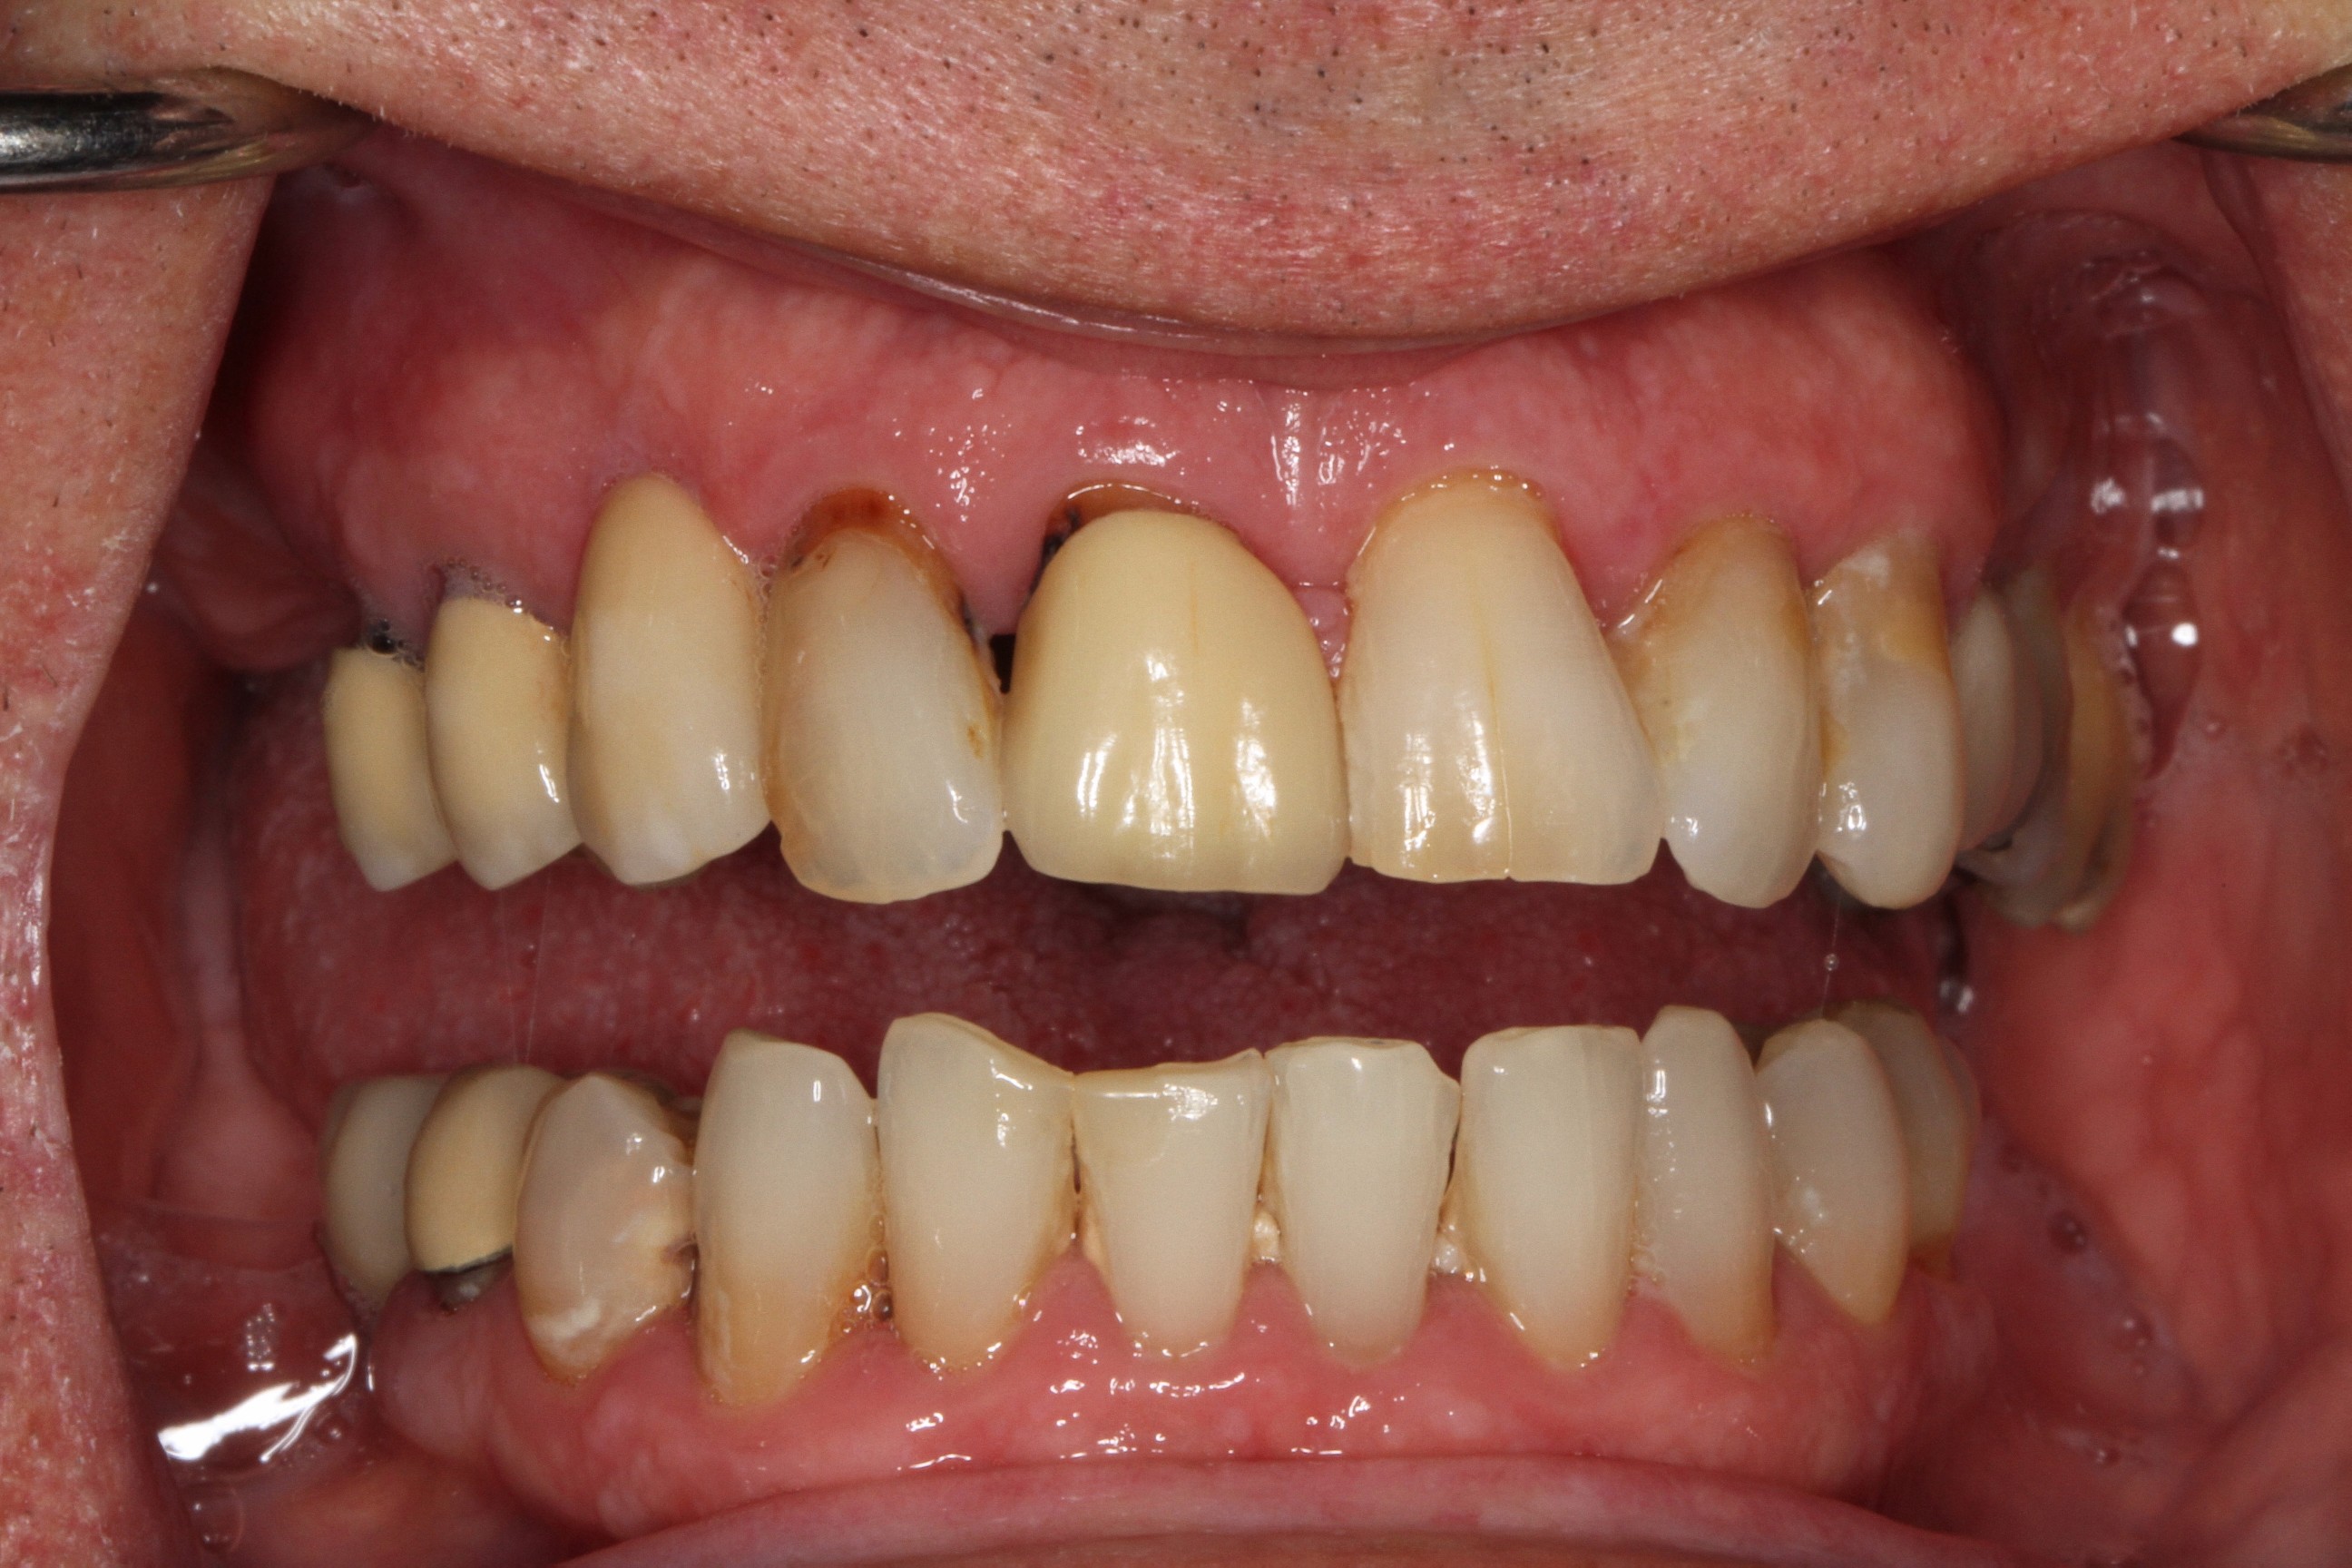

Lenny

Full Mouth Reconstruction with Upper & Lower Arch Replacement

“Lenny presented with advanced periodontal disease which was causing extensive bone resorption and tooth mobility. His teeth were getting loose and general dental health was poor. Eventually he suffered with a severe gum infection that caused him excruciating pain and stress. Lenny was extremely fearful of the dentist and the fact that PGA Dentistry offered IV sedation was a huge benefit.”

Advanced periodontitis leading to bone resorption & tooth mobility.